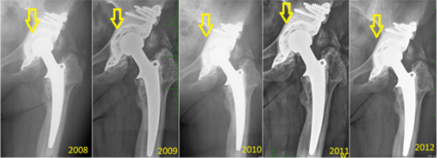

The migration occurred proximally, with breakage of the proximal screws and migration of the plate (from 2009). Then, a mixture of the screws is seen in the bottom of the joint space (2010) and luxation (2012). In the same year (2012), we re-admitted the patient for re-reimplantation and implanted a hemispheric modulus with excenter and larger revision stem. In Figure 6, a case of mechanical loosening of the BS plate is presented. This event does not, generally, lead to positional plate loosening. Instead, the plate protrudes into the pelvis slightly, though it is still capable of full-weight bearing.

Figure 6: Representative case of mechanical loosening of the BS plate involving the proximal region. No BS plate failure occurred in such a case. Yellow arrows denote the stability of the implant at 4-year post-implantation.